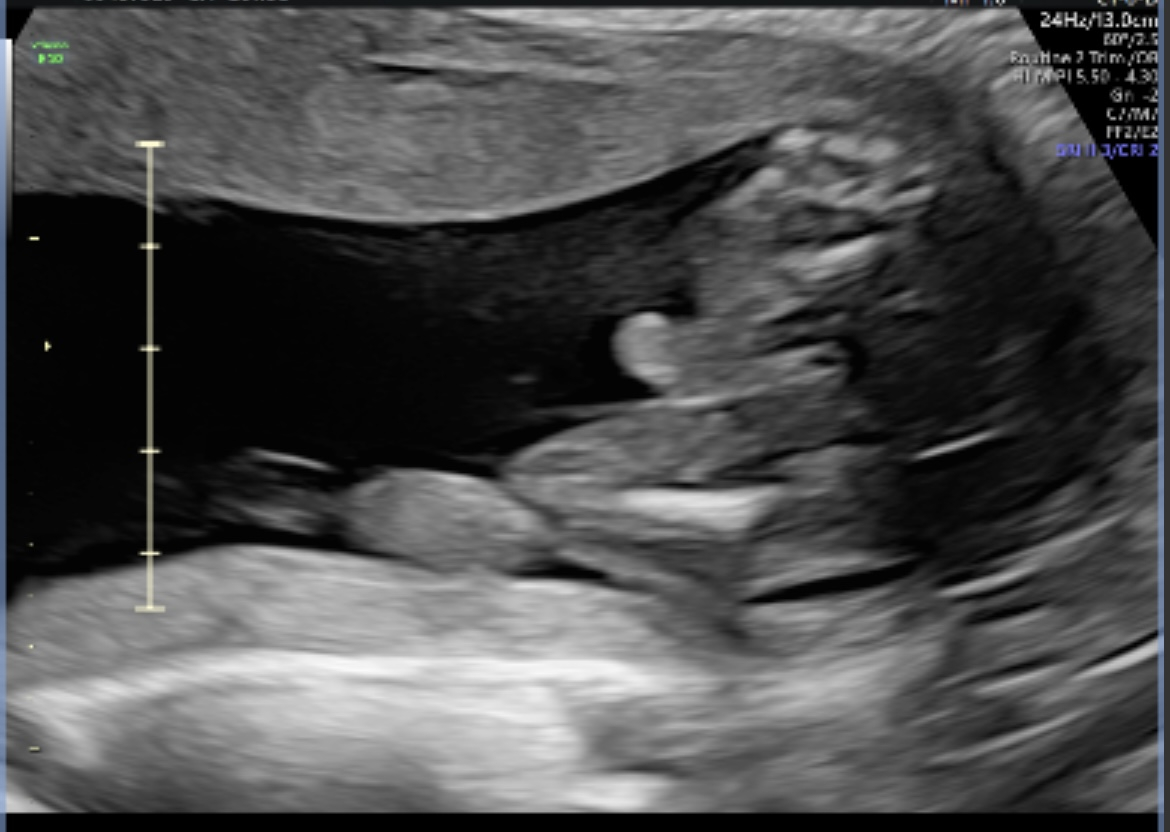

Little boy is 24 weeks today 🩵

Report